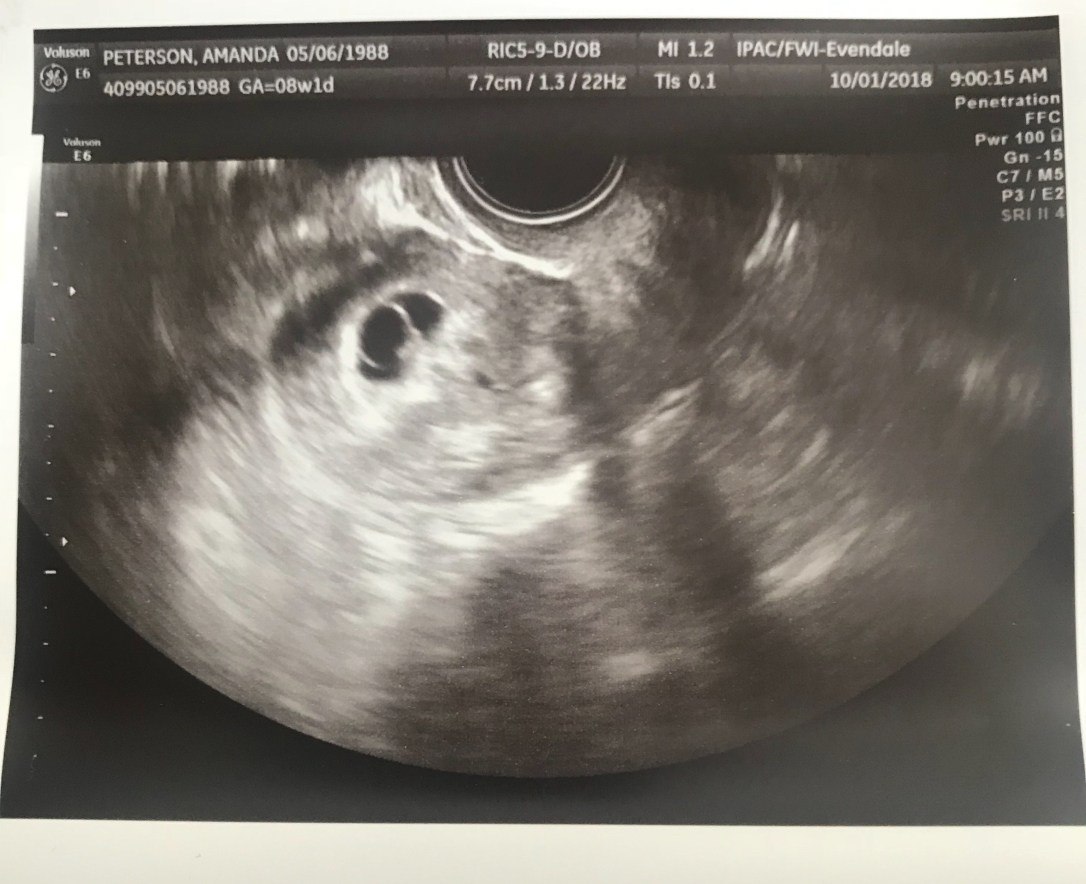

8 Weeks + 1 Day? (October 1)

We went in today for a follow-up ultrasound. She calls us back, and first tried to do the ultrasound on my belly. It was too small, so she had to do it trans-vaginally. Then, it sounded exactly the same as the week before: “You’re measuring about six weeks. It’s too early to detect a heartbeat. What we normally do is schedule a repeat scan for a week from now.” Tears welling in my eyes, I had to correct her. “That’s what you told us last week.” She didn’t say much else. I requested a photo of the ultrasound.

As I got dressed, I began crying. Thinking, there’s no way she’s right. She has to be wrong. I haven’t had a single symptom of miscarriage. I heard the ultrasound tech speaking with my doctor in the hallway. Apologizing, she didn’t realize she had already scanned me last week. A minute later, the doctor came in. “It’s important for you to know, it was nothing you did.” I felt numb. I didn’t cry, I didn’t show any emotion, I am pretty sure I was in shock. She never actually said the words, “You’re miscarrying.” I asked, “So there’s no possible chance this pregnancy will progress?” The short answer: No. We began discussing options, and I cut her off, “I need a D&C.” I knew, from my previous missed miscarriage, that my body would not expel the remains on its own or with the help of Cytotec, so a D&C was truly my only option. Noting that I still feel very much pregnant, she went on to say that was a good thing, that my body is producing all the right hormones, and clinging to this pregnancy as it should.